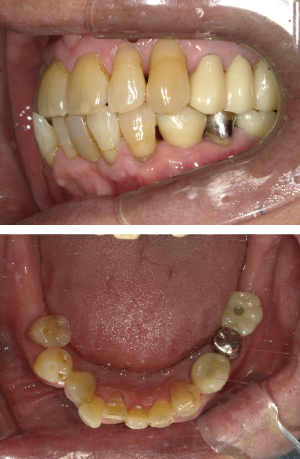

インプラント治療(左上5ソケット・GBR 右上2左上13GBR)

| 年代・性別 | 50代・男性 |

| 主訴 | 入れ歯だと咬めなくてつらい。 |

| 部位 | 上顎②1①2③4⑤Br |

| 治療期間 | 約9ヶ月 |

| 費用 | ¥1,794,100(税込) |

| 副作用・リスク |

|